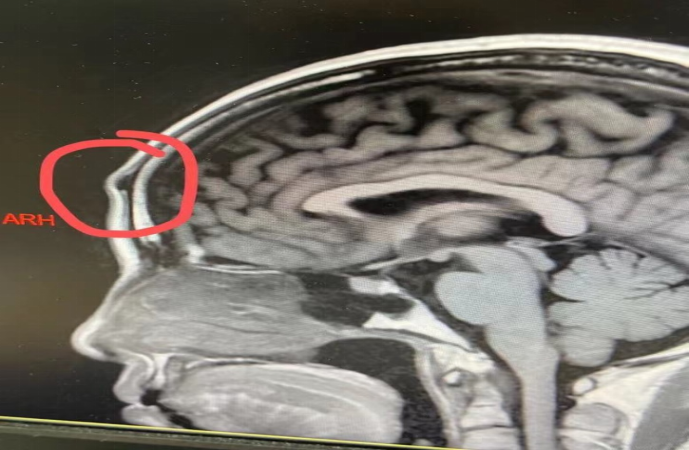

为不影响患者的颜值,术后不留疤,沈建忠主任主持神经外科手术团队术前讨论,确定了在前额发际线内3.5cm实行切口,使用神经内镜辅助操作把患者的额骨骨瘤切除的手术方式。在科室副主任王继斌医师的带领下,神经外科内镜团队为患者实施了内镜下额骨肿瘤磨除术,术中过程顺利。